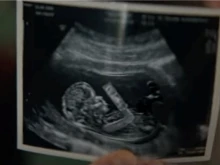

The ad, which aired during Super Bowl LVII on Feb. 12, 2023, featured a sonogram of a preborn baby.

Pringles commercial airs most pro-life ad of the Super Bowl

The sonogram image prominently featured in the Super Bowl was praised by pro-lifers as bringing attention to the humanity of... Read more